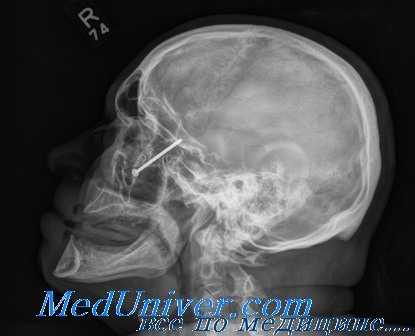

На рентгенограммах черепа слева - инородное тело (пуля) в верхней челюстной пазухе, дефект нижней стенки орбиты около 0,5 см.

Консультация нейрохирурга: ЗЧМТ нет, огнестрельное ранение головы без проникновения в полость черепа. Консультация челюстно - лицевого хирурга (ЧЛХ): инородное тело верхней челюстной пазухи, перелом нижней стенки глазницы слева; психиатра: нарушение адаптации, депрессивный синдром, неудавшийся суицид; травматолога: несвежие резаные раны предплечий правой и левой руки.

Под эндотрахеальным наркозом офтальмологами проведена ревизия глазного яблока, раны брови: ран склеры во всех сегментах не обнаружено, рана брови проникает в орбиту на 3,0 см, промыта, дренирована. Одновременно ЧЛХ внутри ротовым доступом удалено инородное тело (пуля): 2,4 х 1,0 х 0,7 см, костные осколки нижней стенки глазницы и передней стенки верхнечелюстной пазухи.